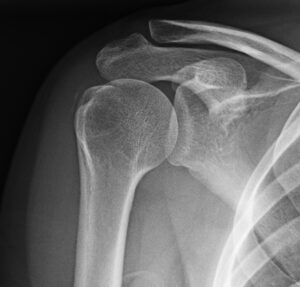

La radiografía nos permite evaluar la localización, la morfología, el tamaño y la densidad de las calcificaciones, pudiendo así clasificarlas. En el hombro, las proyecciones más útiles para tales efectos son la anteroposterior, outlet y las anteroposterior con rotación interna y externa.